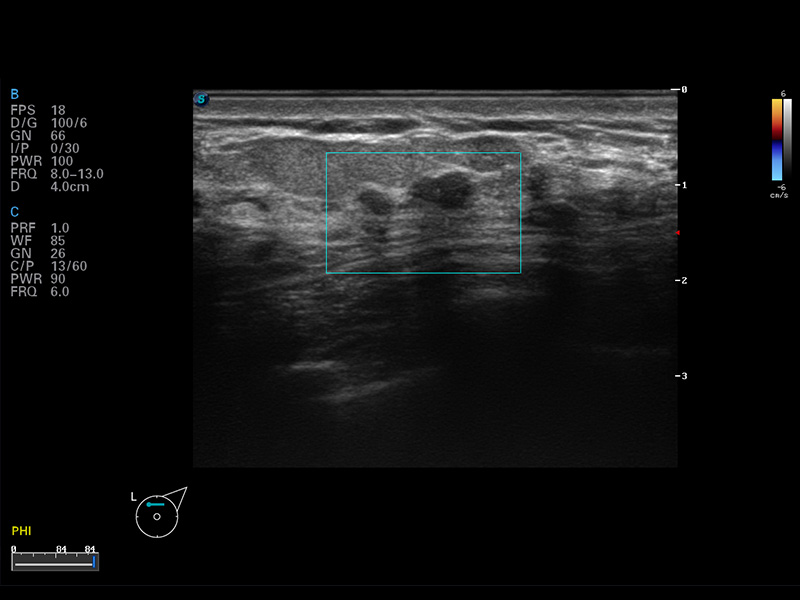

S8 EXP便携式彩色多普勒超声诊断仪是银河集团官网研发的高端全身应用型便携彩超。高通道的VIS平台融合可视化(Visual)、智能化(Intelligent)和人性化(Smart)的特点,配以银河集团官网自主研发生产的探头大家族,使您能够快速、准确的获得病人信息,提高工作效率的同时减轻疲劳。

μ-Scan微米成像